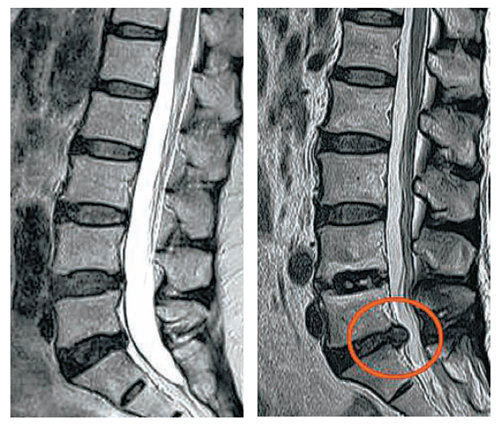

이번 포스팅에서 허리디스크에 좋은 운동 10가지에 대하여서 알아볼꺼에요. 허리는 우리 몸무게의 약 60%를 지탱하고 있습니다. 상당히 귀중한 육체 부위에요.

사무실이나 집에서 컴퓨터나 노트북을 하는 직장인들이 많다고 해서지면서 허리디스크 통증을 호소하는

분들이 불어나고 있다고 합니다.

허리디스크에 대해 아직 살펴보지 못하셨다면 허리디스크가 어느 부위를 말하는지 확인하시고 시기에 맞추어 운동하여 주십시요.